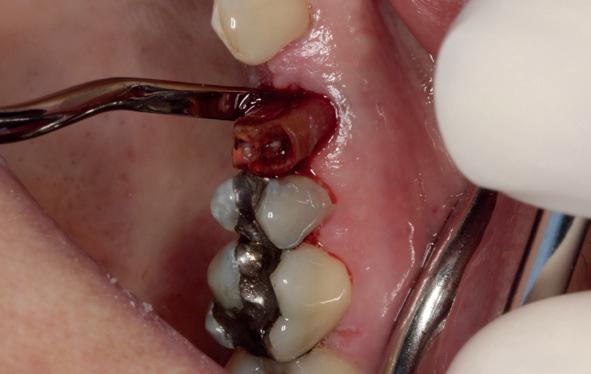

Afbeelding 1 en 2. Een immediate placement (afbeelding 1) is maar weinig invasief en zal weinig nalast geven. Bij een uitgebreide botopbouw (afbeelding 2) daarentegen is de wond veel groter en kan er meer nalast verwacht worden.

Bij uitgebreidere behandelingen zoals botbreedteen/of hoogteherstel is er vaak sprake van een groter chirurgisch gebied. De mucosa en het botvlies (periost) worden verder afgeschoven en vaak is het noodzakelijk om het rijkelijk doorbloede periost in te snijden (klieven) om de mucosa weer spanningsvrij te kunnen hechten na de ingreep. Dit heeft meer bloeding en zwelling tot gevolg, hetgeen weer meer druk geeft op het wondgebied. Ook de patiënt zelf is

In deze casus is extractie van de 37 geïndiceerd in verband met een fistel en restpockets, zoals zichtbaar op de röntgenfoto’s (afbeelding 1). Duidelijk te zien is de forse peri-apicale ontsteking en het botverlies bij de 37, dat zowel richting buccaal als linguaal doorloopt. De 37 wordt atraumatisch verwijderd. Er is aan de linguale zijde veel bot verloren en er is sprake van een perforatie aan de buccale zijde.

Er wordt besloten om botmateriaal te plaatsen in de extractie-alveole. Vervolgens wordt het afgesloten met een titanium versterkt d-PTFE membraan (afbeelding 2). Na vier weken wordt het membraan verwijderd.